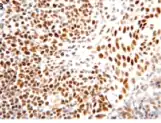

![]() | |

| Micrograph showing cutaneous T-cell lymphoma. H&E stain | |